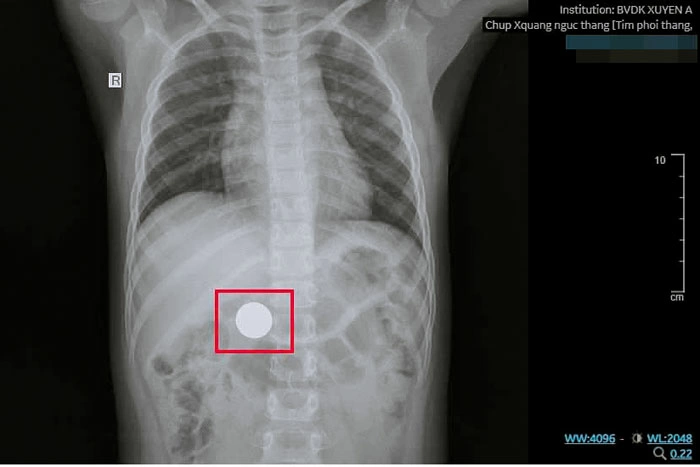

Chấn thương nặng sau “thử thách” nhét dây mạng máy tính vào niệu đạo 16:33, 14/01/2026 Thời gian qua, Khoa Ngoại Tổng hợp Bệnh viện Nhi Đồng TP Cần Thơ tiếp nhận và xử lý nhiều trường hợp trẻ em bị tai nạn do thực hiện các thử thách trên mạng xã hội. Đây là tình trạng rất đáng báo động cho các bậc phụ huynh.